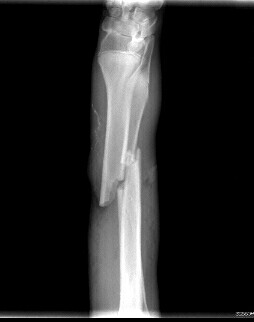

• 흉, 복부 방사선 검사 방사선 검사는 골격계의 이상을 진단하는 기초검사입니다. 방사선 검사를 통해 골격계의 선천적 이상 등을 진단하게 됩니다. 흉부 방사선 사진을 통해 기관의 이상 유무 판결, 심장 크기 및 위치의 변화 등을 진단하게 됩니다. 복부 방사선을 통해 방광의 결석, 복강 실질장기의 크기 및 위치 변화 등을 진단할 수 있습니다. 또한, 드물게 발생하는 선천적 결손증의 일부를 진단하게 됩니다.

• 흉, 복부 방사선 검사 노령화가 진행됨에 따라 종양성 질환도 증가하게 됩니다. 종양의 발생 유무와 전이여부를 판단하기 위해 흉강과 복강 방사선 사진이 필요합니다. 암컷의 경우 장년기에 자주 발생하는 질환이 자궁축농증과 유선의 종양입니다. 방사선 사진으로 질병의 조기진단이 가능합니다. 수컷의 경우는 전립선의 이상으로 발생할 수 있는 질환을 진단할 수 있습니다. 종양과 비뇨생식기계질환의 조직 진단으로 건강한 생활을 영위할 수 있도록 도움을 주게 됩니다.

• 흉, 복부 방사선 검사 노령기의 질환 중 상당수가 종양성 질병과 관련이 있습니다. 정기적인 방사선 검사를 통해 종양성 질환의 발병 유무 및 전이여부를 평가합니다. 심장의 외형변화, 폐 실질의 이상 변화 등을 검사하고 지속적으로 관리하여야 합니다. 체표의 종양성 질환은 눈으로 관찰이 가능하지만 심부의 종양은 관찰이 어렵습니다. 심부의 종양성 변화를 비교적 쉽게 관찰할 수 있는 검사법이 방사선검사입니다. 노령기는 약 6개월단위 정기 검사가 필요합니다.